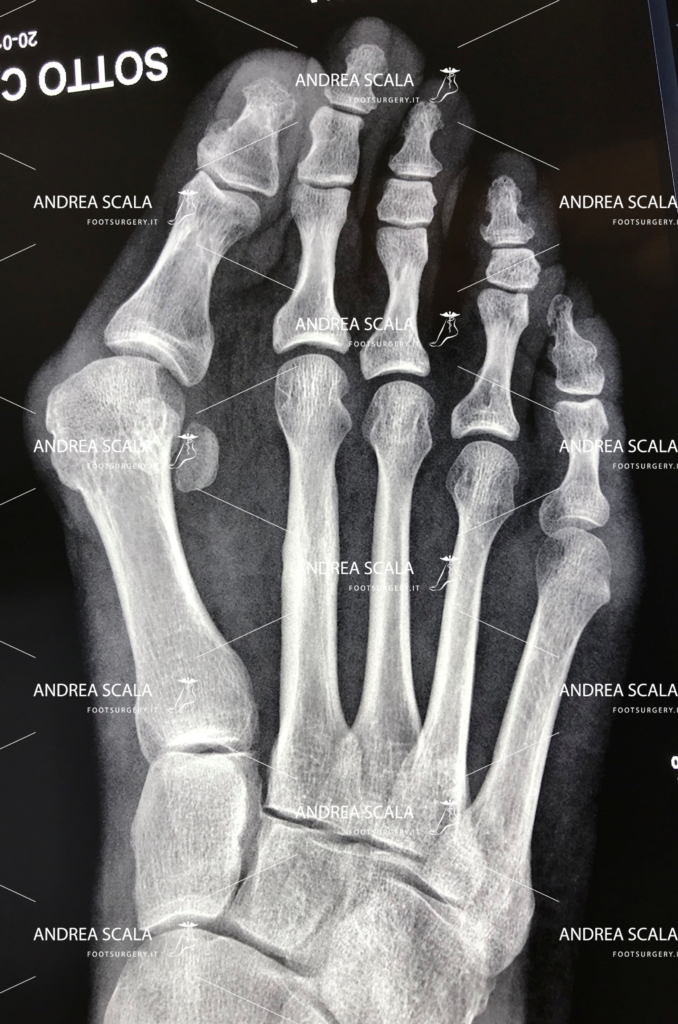

Dopo la prima visita, vengono effettuate tutte le indagini diagnostiche del caso che possono portare o meno all’operazione. La prima visita è indicativa per il medico che potrà osservare il paziente in posizione eretta e durante la deambulazione, concentrandosi su appoggio di avampiede e retropiede. L’esame radiografico dei due piedi sottocarico è di fondamentale importanza. In alcuni casi può essere opportuno effettuare anche altri esami come Tac, Risonanza magnetica o Ecografia.

L’aspetto più importante è il grande spostamento in senso laterale della testa del 1° metatarso, questo fa sparire la “cipolla” di più e meglio degli altri interventi. Rimuovendo lo spostamento patologico del 1° metatarso, in corrispondenza della “cipolla”. Il piede assume la forma desiderata dalla paziente.

Dopo aver eseguito l’osteotomia (intervento chirurgico di taglio dell’osso) del 1° metatarso viene corretta la disposizione delle ossa, dei legamenti, dei tendini e dei nervi, con il conseguente riallineamento dell’alluce rispetto alle altre dita del piede. A questo punto si introduce all’interno un sottile filo metallico (1,5 mm). Non si mettono fili metallici esterni tipo “spiedino”. Il filo metallico interno fornisce la garanzia che l’alluce operato non tornerà mai più in valgo. Il dato saliente che caratterizza l’intervento è che la testa del 1° metatarso viene esattamente posizionato sopra i due sesamoidi. Pochi altri interventi hanno la medesima accuratezza, nessuno con tecnica percutanea.